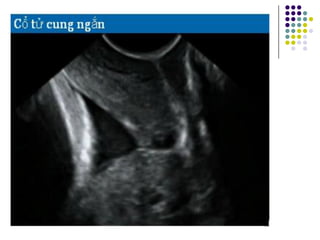

Đo chiều dài CTC: CTC cong

- CTC bị uốn cong khi đo chiều dài CTC vẫn

đo một đường thẳng nối từ lỗ trong ra lỗ

ngoài

- Cách đo này thì chiều dài CTC không thể

ngắn hơn so với đo dọc theo đường NM của

kênh CTC

- Phương pháp này không quan trọng vì CTC

ngắn thì luôn luôn là một đường thẳng